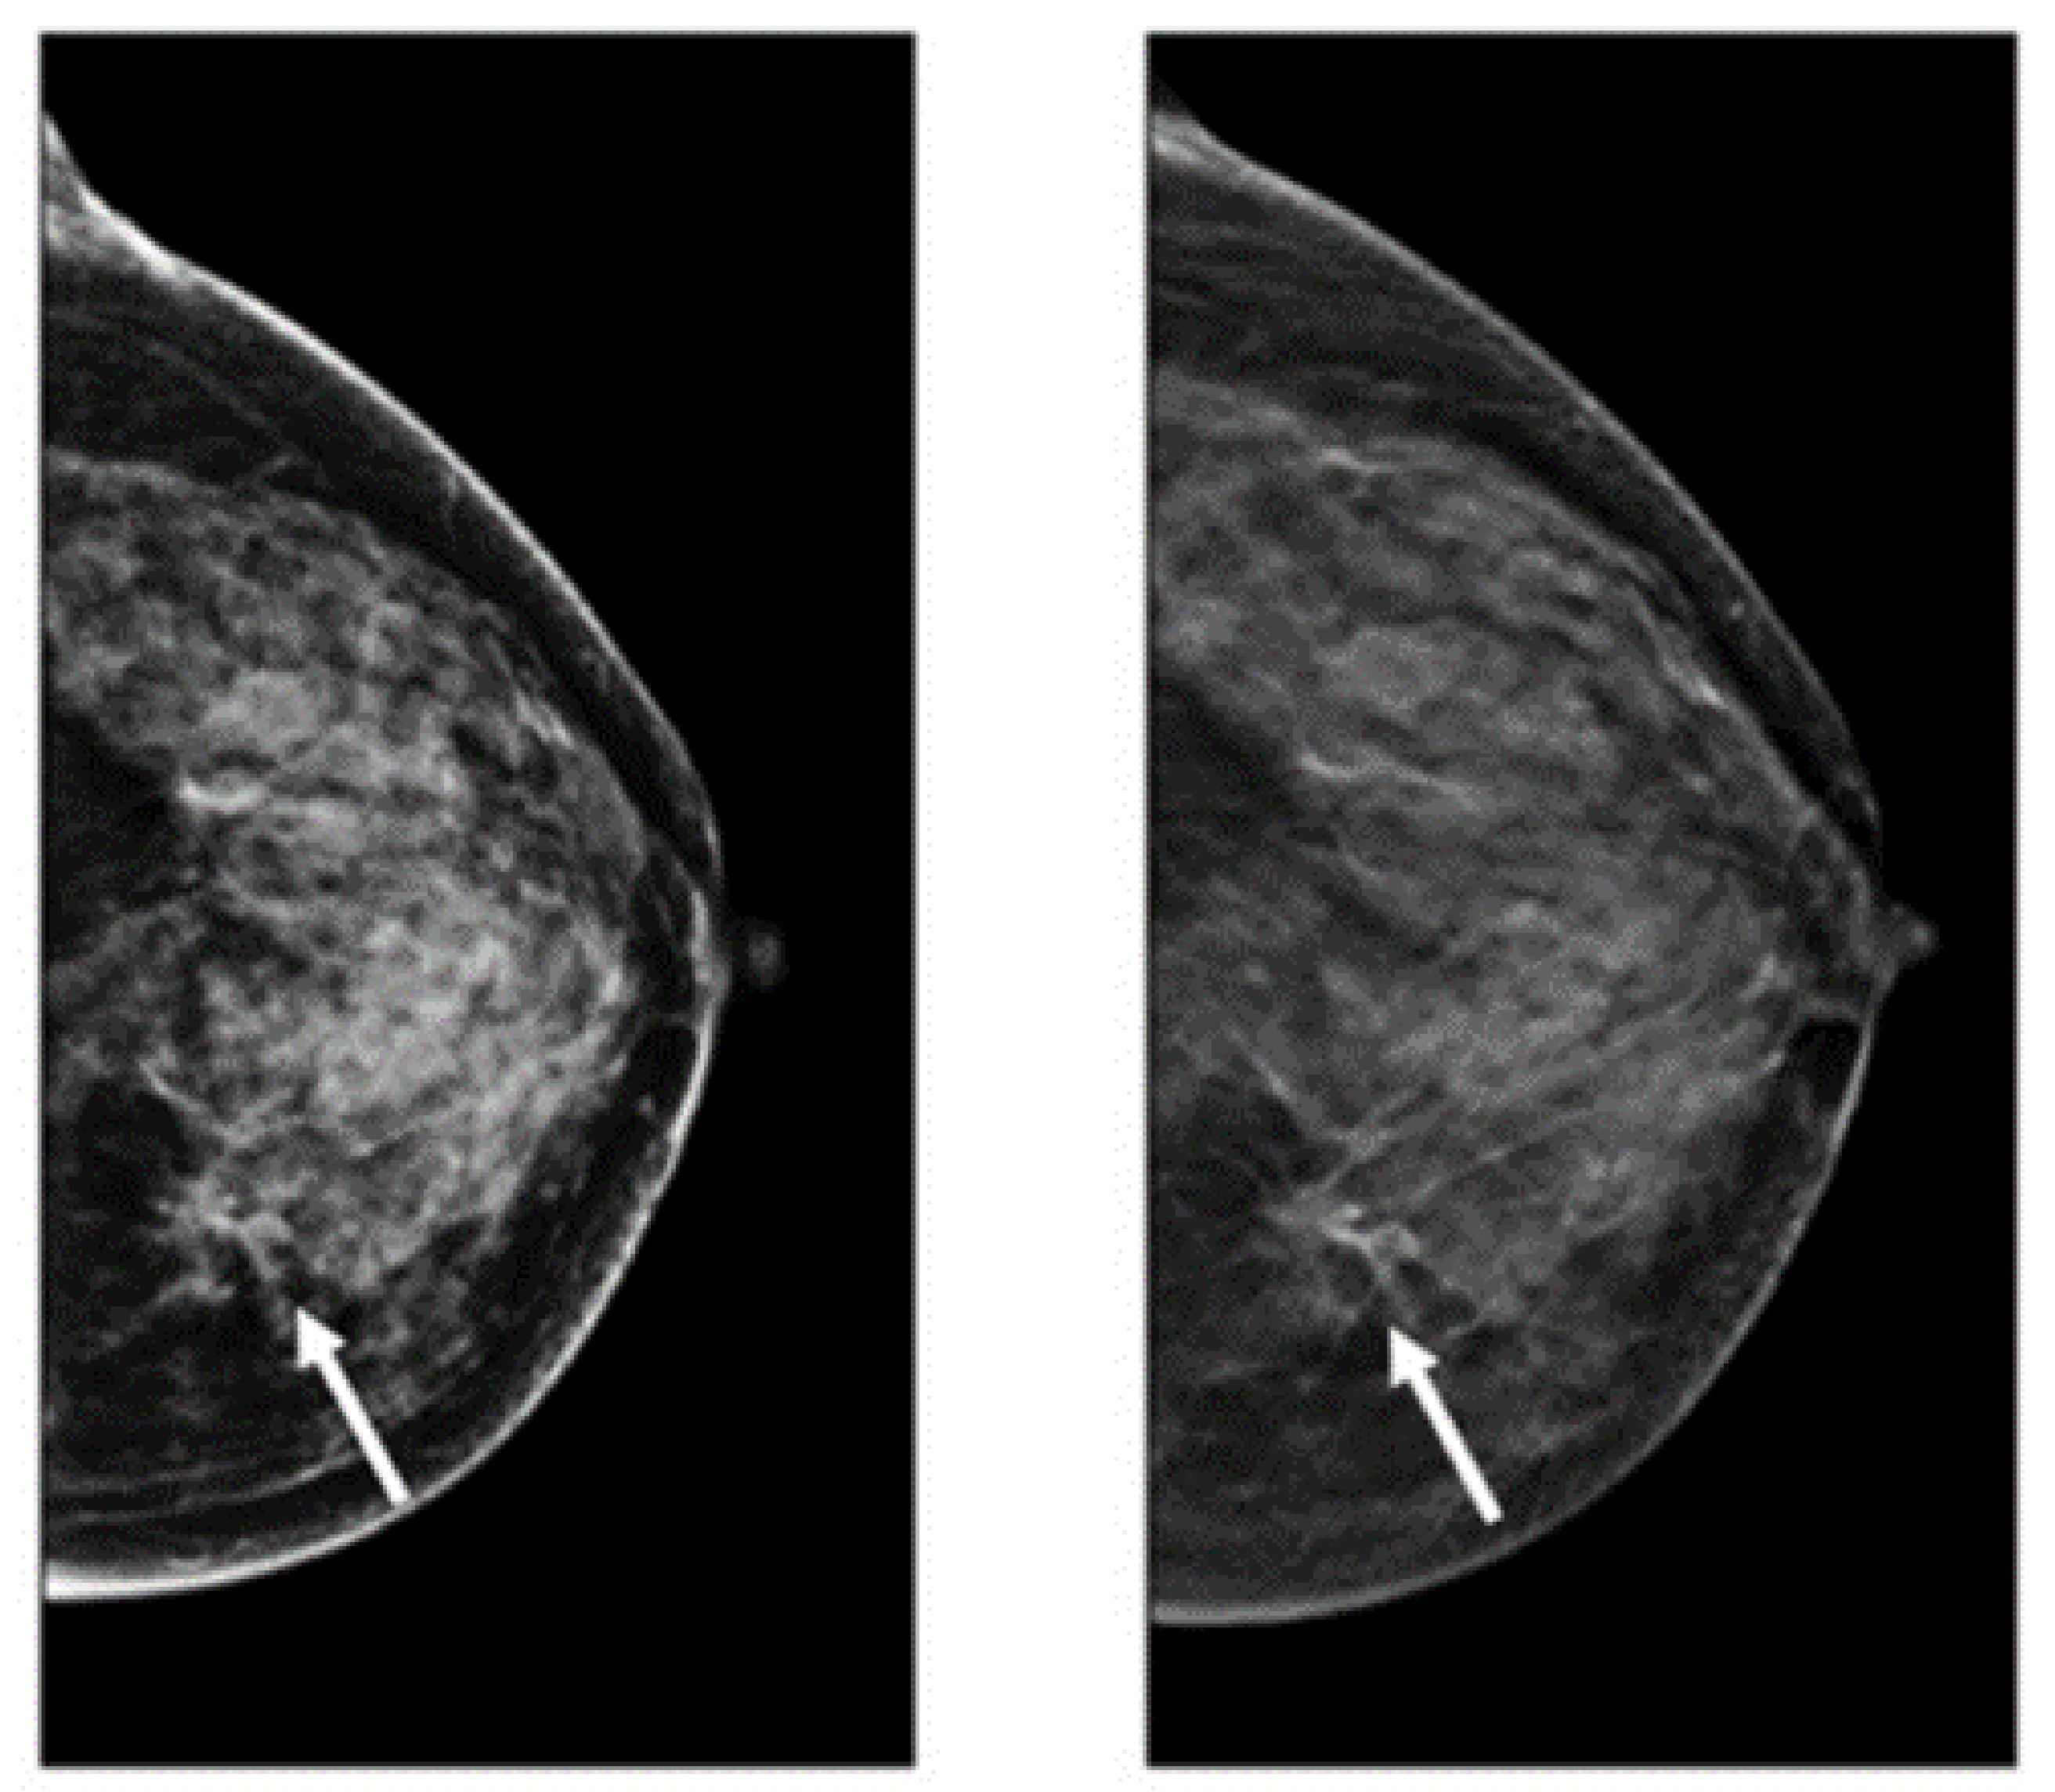

The advantages of mammograms, such as being cost-effective to detect tumors in the initial stage before development, mean that MMs are the most promising imaging screening technique in clinical practice. MMs are generally images of breasts produced by low-intensity X-rays (Figure 1) [33]. In this imaging modality, cancerous regions are brighter and more clear than other parts of breast tissue, helping to detect small variations in the composition of the tissues; therefore, it is used for the diagnosis and analysis of breast cancer [34,35] (Figure 1). Although MMs are the standard approach for breast cancer analysis, it is an inappropriate imaging modality for women with dense breasts [36], since the performance of MMs highly depends on specific tumor morphological characteristics [36,37]. To deal with this problem, using automated whole breast ultrasound (AWBU) or other methods are suggested with MMs to produce a more detailed image of breast tissues [38].

Figure 1. Example of breast cancer images using traditional film MMs. Reprinted/adapted with permission from [49]. 2021, Elsevier.